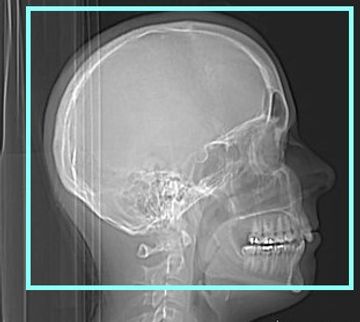

Helical acquisition. Supine. All sinuses done as Fusion protocol. FOV to include vertex of head.

2.5 X 2.0 GE standard and bone / 2.0 X 2.0 Siemens standard and bone

Reformats: 0.625x0.625 GE Standard and bone/ 0.75x0.7 Siemens standard and bone

Coronal 1.0 x 1.0 mm standard and bone

Sagittal 2.0 X 2.0 mm standard and bone

Coronal 3.0 X 3.0 mm bone for filming ( 4 across by 5 down format for film )